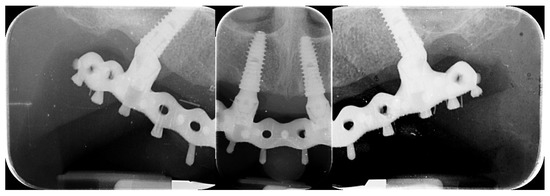

- Accuracy was tested by means of direct vision and tactile sensation, performed by applying alternately pressure on the aluminum try-in, and then the definitive metal framework (Alternate Pressure Technique), secured without screws, to determine if any movement occurs. In addition, the one-screw test proposed by Jemt and co-workers was performed in case of doubts occurred [11]. No discrepancy of the radiopaque, aluminum try-in, secured with only one screw tightened, was observed [11]. Peri-apical radiographs were taken if needed. The same operator (MT) performed both tests using a microscope magnification (10× to 16×);